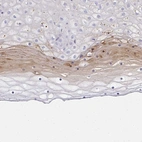

Immunohistochemical staining of human cervix, uterine shows moderate cytoplasmic and nuclear positivity in a fraction of superficial squamous epithelial cells.